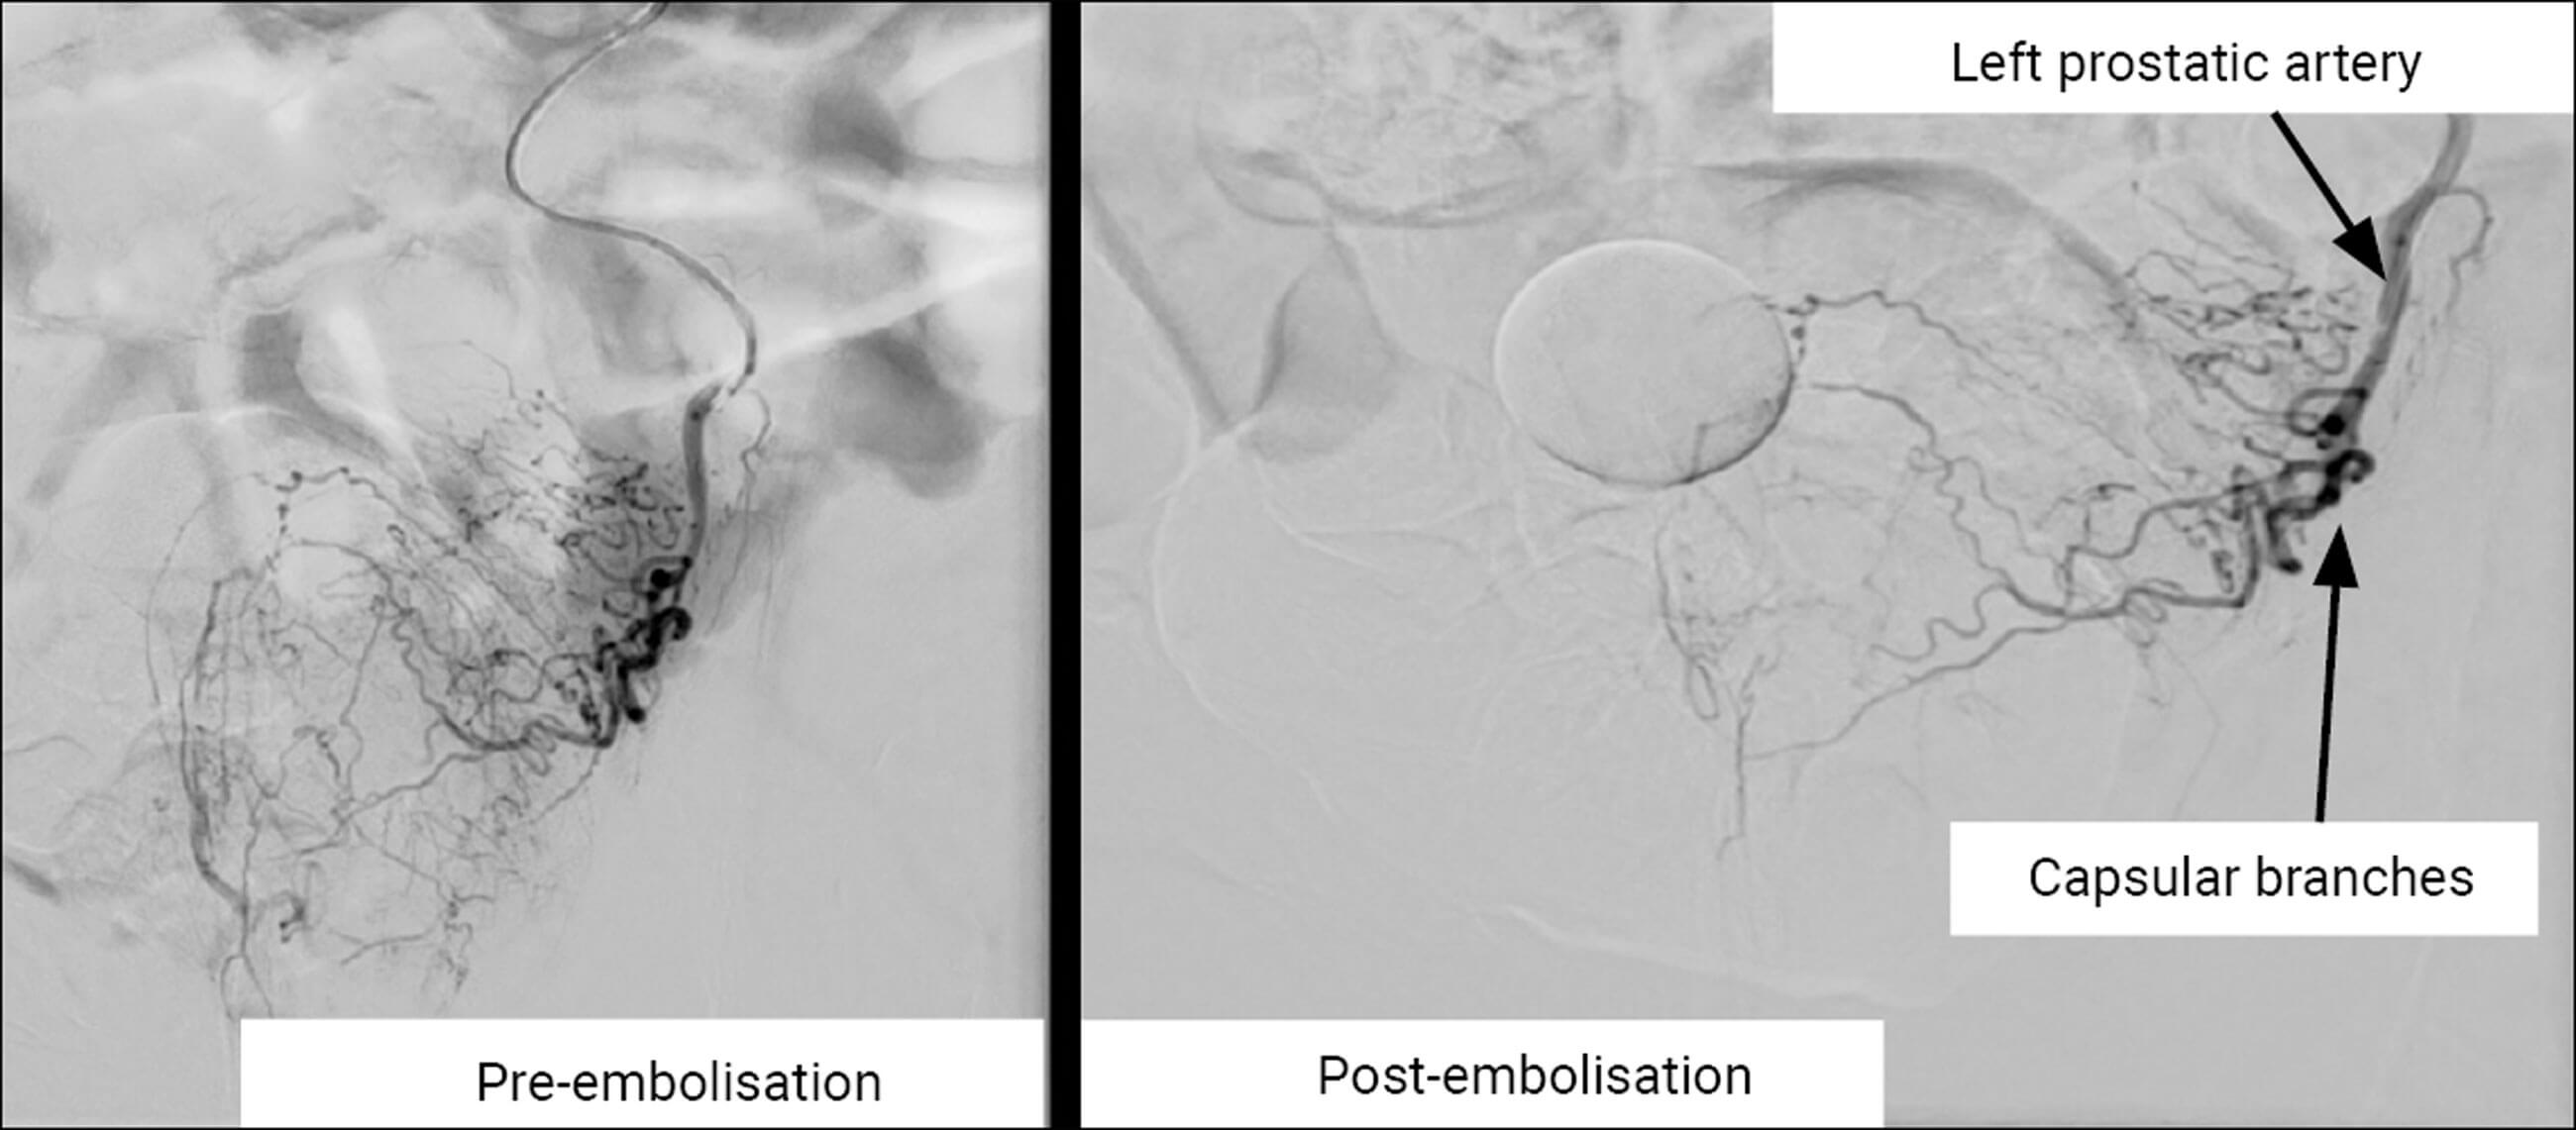

An 86-year-old male presented with visible haematuria and suprapubic pain. He had a history of diabetes, heart failure, benign prostatic hypertrophy, aortic valve replacement, deep vein thrombosis (DVT) and atrial fibrillation (AF) and was anticoagulated on a non-VKA oral anticoagulant (NOAC). Despite conservative measures of washouts and irrigation via a three-way catheter, the bleeding continued. Using the arteriogram, the source of bleeding was identified, with interventional radiological guidance. Interventional radiology then attempted prostate artery embolisation to contain the bleeding. The left prostatic artery was identified, cannulated and embolised, the right prostate artery failed cannulation due to the presence of an atherosclerotic plaque (Figure 1).

Figure 1.